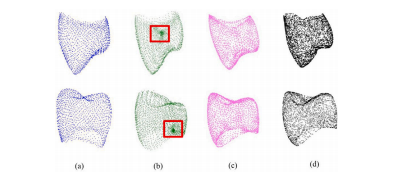

Fig. 4. Comparison of predicted point clouds using our proposed method with previouswork. (𝑎) Illustrates the predicted point cloud using the method by Hosseinimaneshet al. (2023b) with 1536 points. (𝑏) Depicts the same method by Hosseinimanesh et al.(2023b), but with a higher resolution of 3072 points, resulting in a noisier output. (𝑐)Displays the prediction using our proposed model, and (𝑑) represents the ground truth,with both (𝑐) and (𝑑) at the sameresolution of 3072 points

图4:使用我们提出的方法所预测的点云与先前研究成果的比较。(a)展示了使用侯赛尼马内什等人(2023b)的方法预测出的具有1536个点的点云。(b)描绘的是侯赛尼马内什等人(2023b)的相同方法,但分辨率更高,为3072个点,其输出结果包含更多噪声。(c)显示的是使用我们所提出模型的预测结果,(d)代表真实值,(c)和(d)的分辨率相同,均为3072个点。